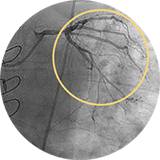

Внутристентовый рестеноз в левой передней нисходящей артерии: ко-регистрация данных с iFR и ВСУЗИ, лазерная атерэктомия, использование баллона с лекарственным покрытием и стентирование.

Внутристентовый рестеноз в огибающей артерии: ко-регистрация с ВСУЗИ, баллонный моделирующий катетер, терапия с помощью баллона с лекарственным покрытием под контролем ВСУЗИ.

Изображение предоставил Аллен Джеремайас, врач. На изображении показано программное обеспечение SyncVision с функцией обнаружения устройств, которое позволяет легко визуализировать особенности проведения терапии.